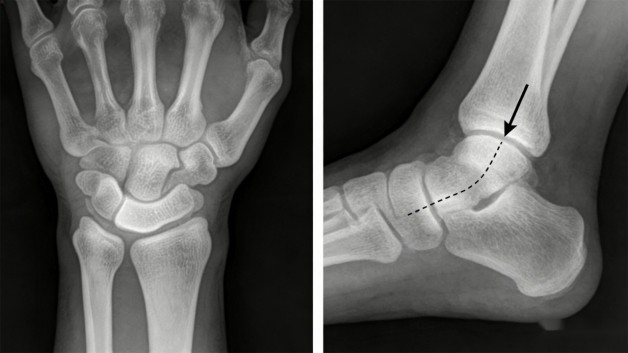

最典型的例子就是手腕舟状骨骨折。如果只拍正面,骨折缝很容易被周围骨头挡得严严实实。这时候,就需要让手腕倾斜到一个特殊角度(医学上称为“舟骨位”)再拍一张,骨折线才能清晰显现出来。少拍这一张,很可能就会漏诊。

比如常见的脚踝扭伤,只拍正面片,可能看不出骨头有没有前后方向的移位。而加拍一张侧面片,就能立刻判断关节是否对齐、骨折块有没有翘起来。这对于决定是打石膏固定还是需要手术复位,至关重要。

(配图1:手腕骨骼重叠示意图)

左图:只拍正位时,腕骨重叠,疑似骨折线被遮挡。

右图:加拍特殊角度后,骨折线(箭头处)清晰可见。

(配图2:脚踝正侧位对比图)

上图:正位片显示骨折(圈出)。

下图:侧位片清晰显示骨折块前后移位(箭头),这是决定治疗方案的关键。